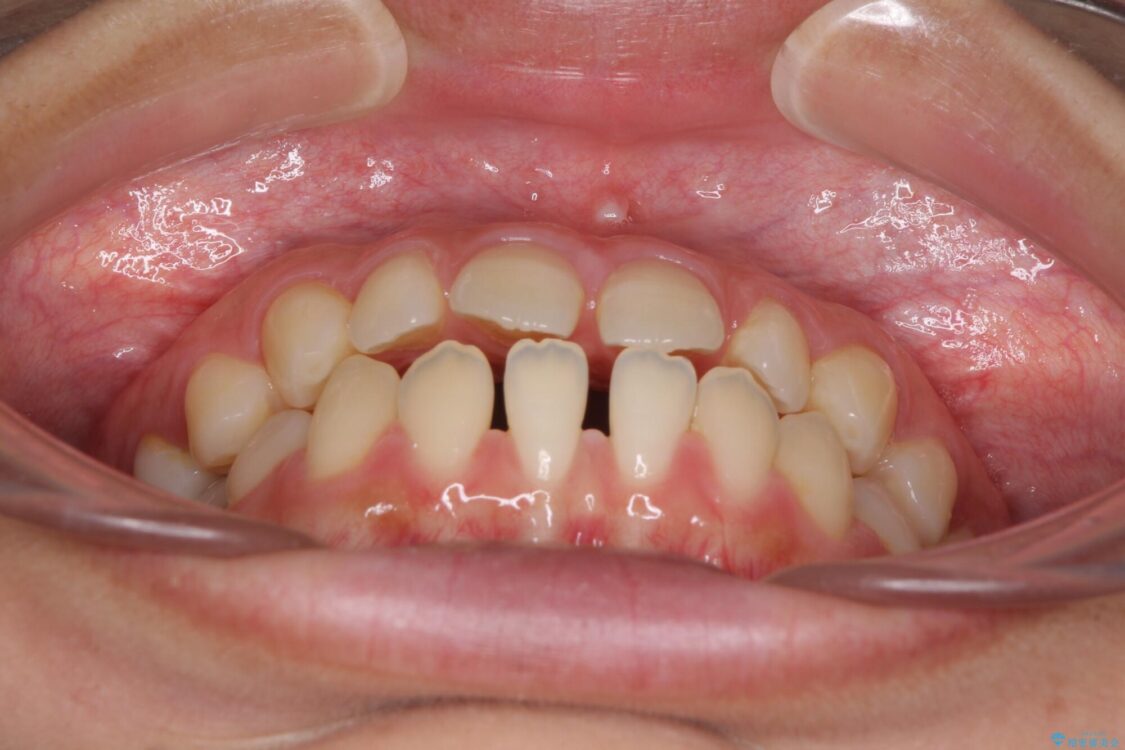

前歯の上下スペースと前歯の隙間を気にして来院された患者様です。

飲み込みや話をするときに舌を突出させる癖が強くあり、それが原因でスペースが空いていました。

舌癖を改善するためのトレーニングを行いながら、インビザラインにより上下の前歯の隙間を閉じていくこととしました。

治療前

• 隙間だらけの歯列 インビザラインで改善 治療前画像